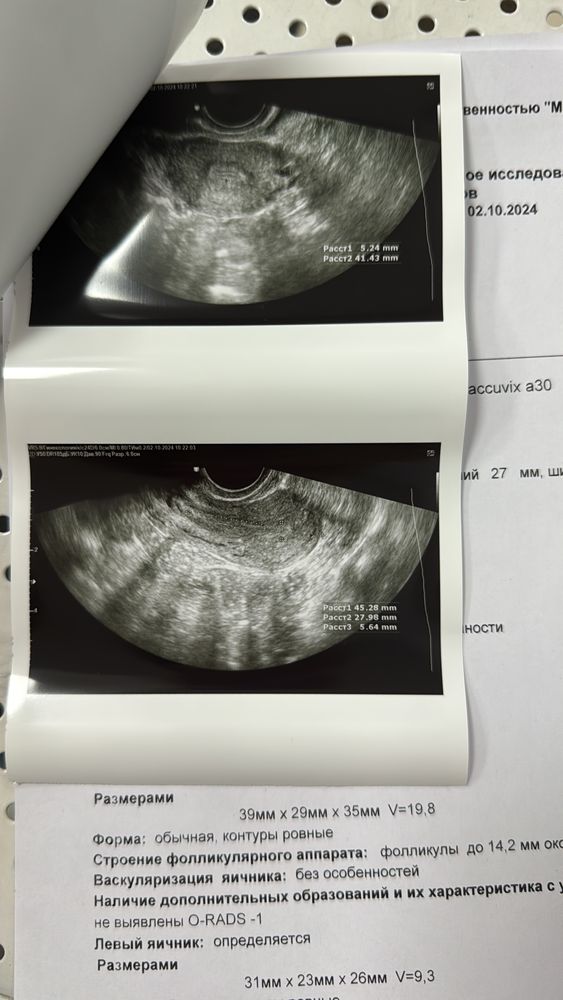

Ландыш Габдуллова в Зачатие год Узи Заключение УЗИ Проверьте пожалуйста, была ли овуляция 28 день цикла, месячные нерегулярные Посмотрите еще 20 записей на эту тему Отменить Ответить Нет ощущений На какое дпо делали УЗИ ? Чаты Беременных Выберите чат: Январята-2026 Февралята-2026 Мартята-2026 Апрелята-2026 Майчата-2026 Июнята-2026 Июлята-2026 Августята-2026